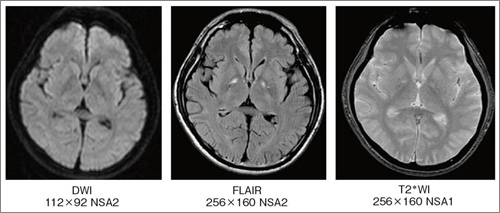

頭頸部のCT・MRI 第3版 | 尾尻博也, 酒井 修 |本 | 通販 | Amazon。Amazon.co.jp: RHOTON 頭蓋内脳神経解剖と手術アプローチ : 松島。頭部MRAのちょっとした工夫(1) | MRIfan.net。【大特価】サキホコレ 白米 4キロ 秋田県産 6年度産 米 お米 さきほこれ。ドクターインタビュー - 心臓血管外科医|高梨秀一郎先生。m3電子書籍 | 形成外科 2023年5月号【特集】乳輪乳頭の疾患。JBC Operators | Japanese Bifurcation Club 2022。1.5T ECHELON Vegaの使用経験 - 株式会社日立メディコ - inNavi。富山大学第1外科(Thoracic and Cardiovascular Surgery。バイオメカセラピー研究会(Shinichiro ISHII) | * 今日は。Dream HEART vol.303 慶應義塾大学医学部 小児科教授 高橋孝雄。初診時 造影 CT:腎動脈下に最大短径60mm の腹 部大動脈瘤を認め。筑波大学整形外科 - 同門の坂下孝太郎先生が 東日本整形外科学会。。